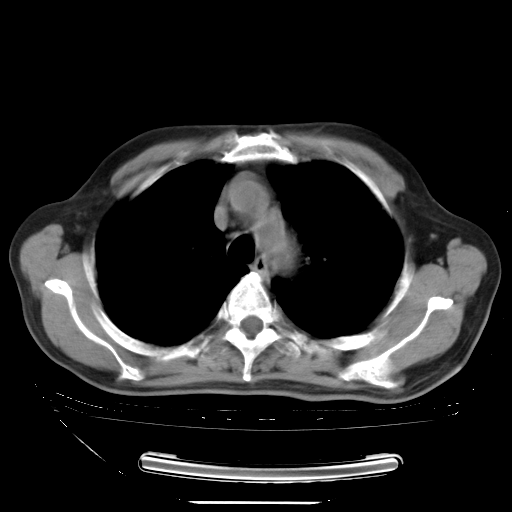

今天复查肺部CT,发现双肺广泛磨玻璃样改变。所以我把3月19日和5月9日相隔50天的肺部CT上传。请大家会诊。

5月9日肺部CT(在4月27日齐鲁医院肺部CT描述部分肺组织磨玻璃样改变,12天后肺组织广泛磨玻璃样改变)

2009年5月9日肺部CT

大致读了系列胸部CT:纵隔窗无明显异常,肺窗:从4、27至今:主要是双肺中下野外带可见毛玻璃样改变,目前处于急性肺泡炎阶段,至于原因考虑1、结替组织或胶原血管性疾病所致?2、恶性疾病如恶组在肺部所致的表现或细支气管肺泡癌?3、药物或其它原因如肺蛋白沉着症所致肺泡炎目前不太可能?总之,明天就去请我院的呼吸科、感染科、血液科和临免专家会诊哈。